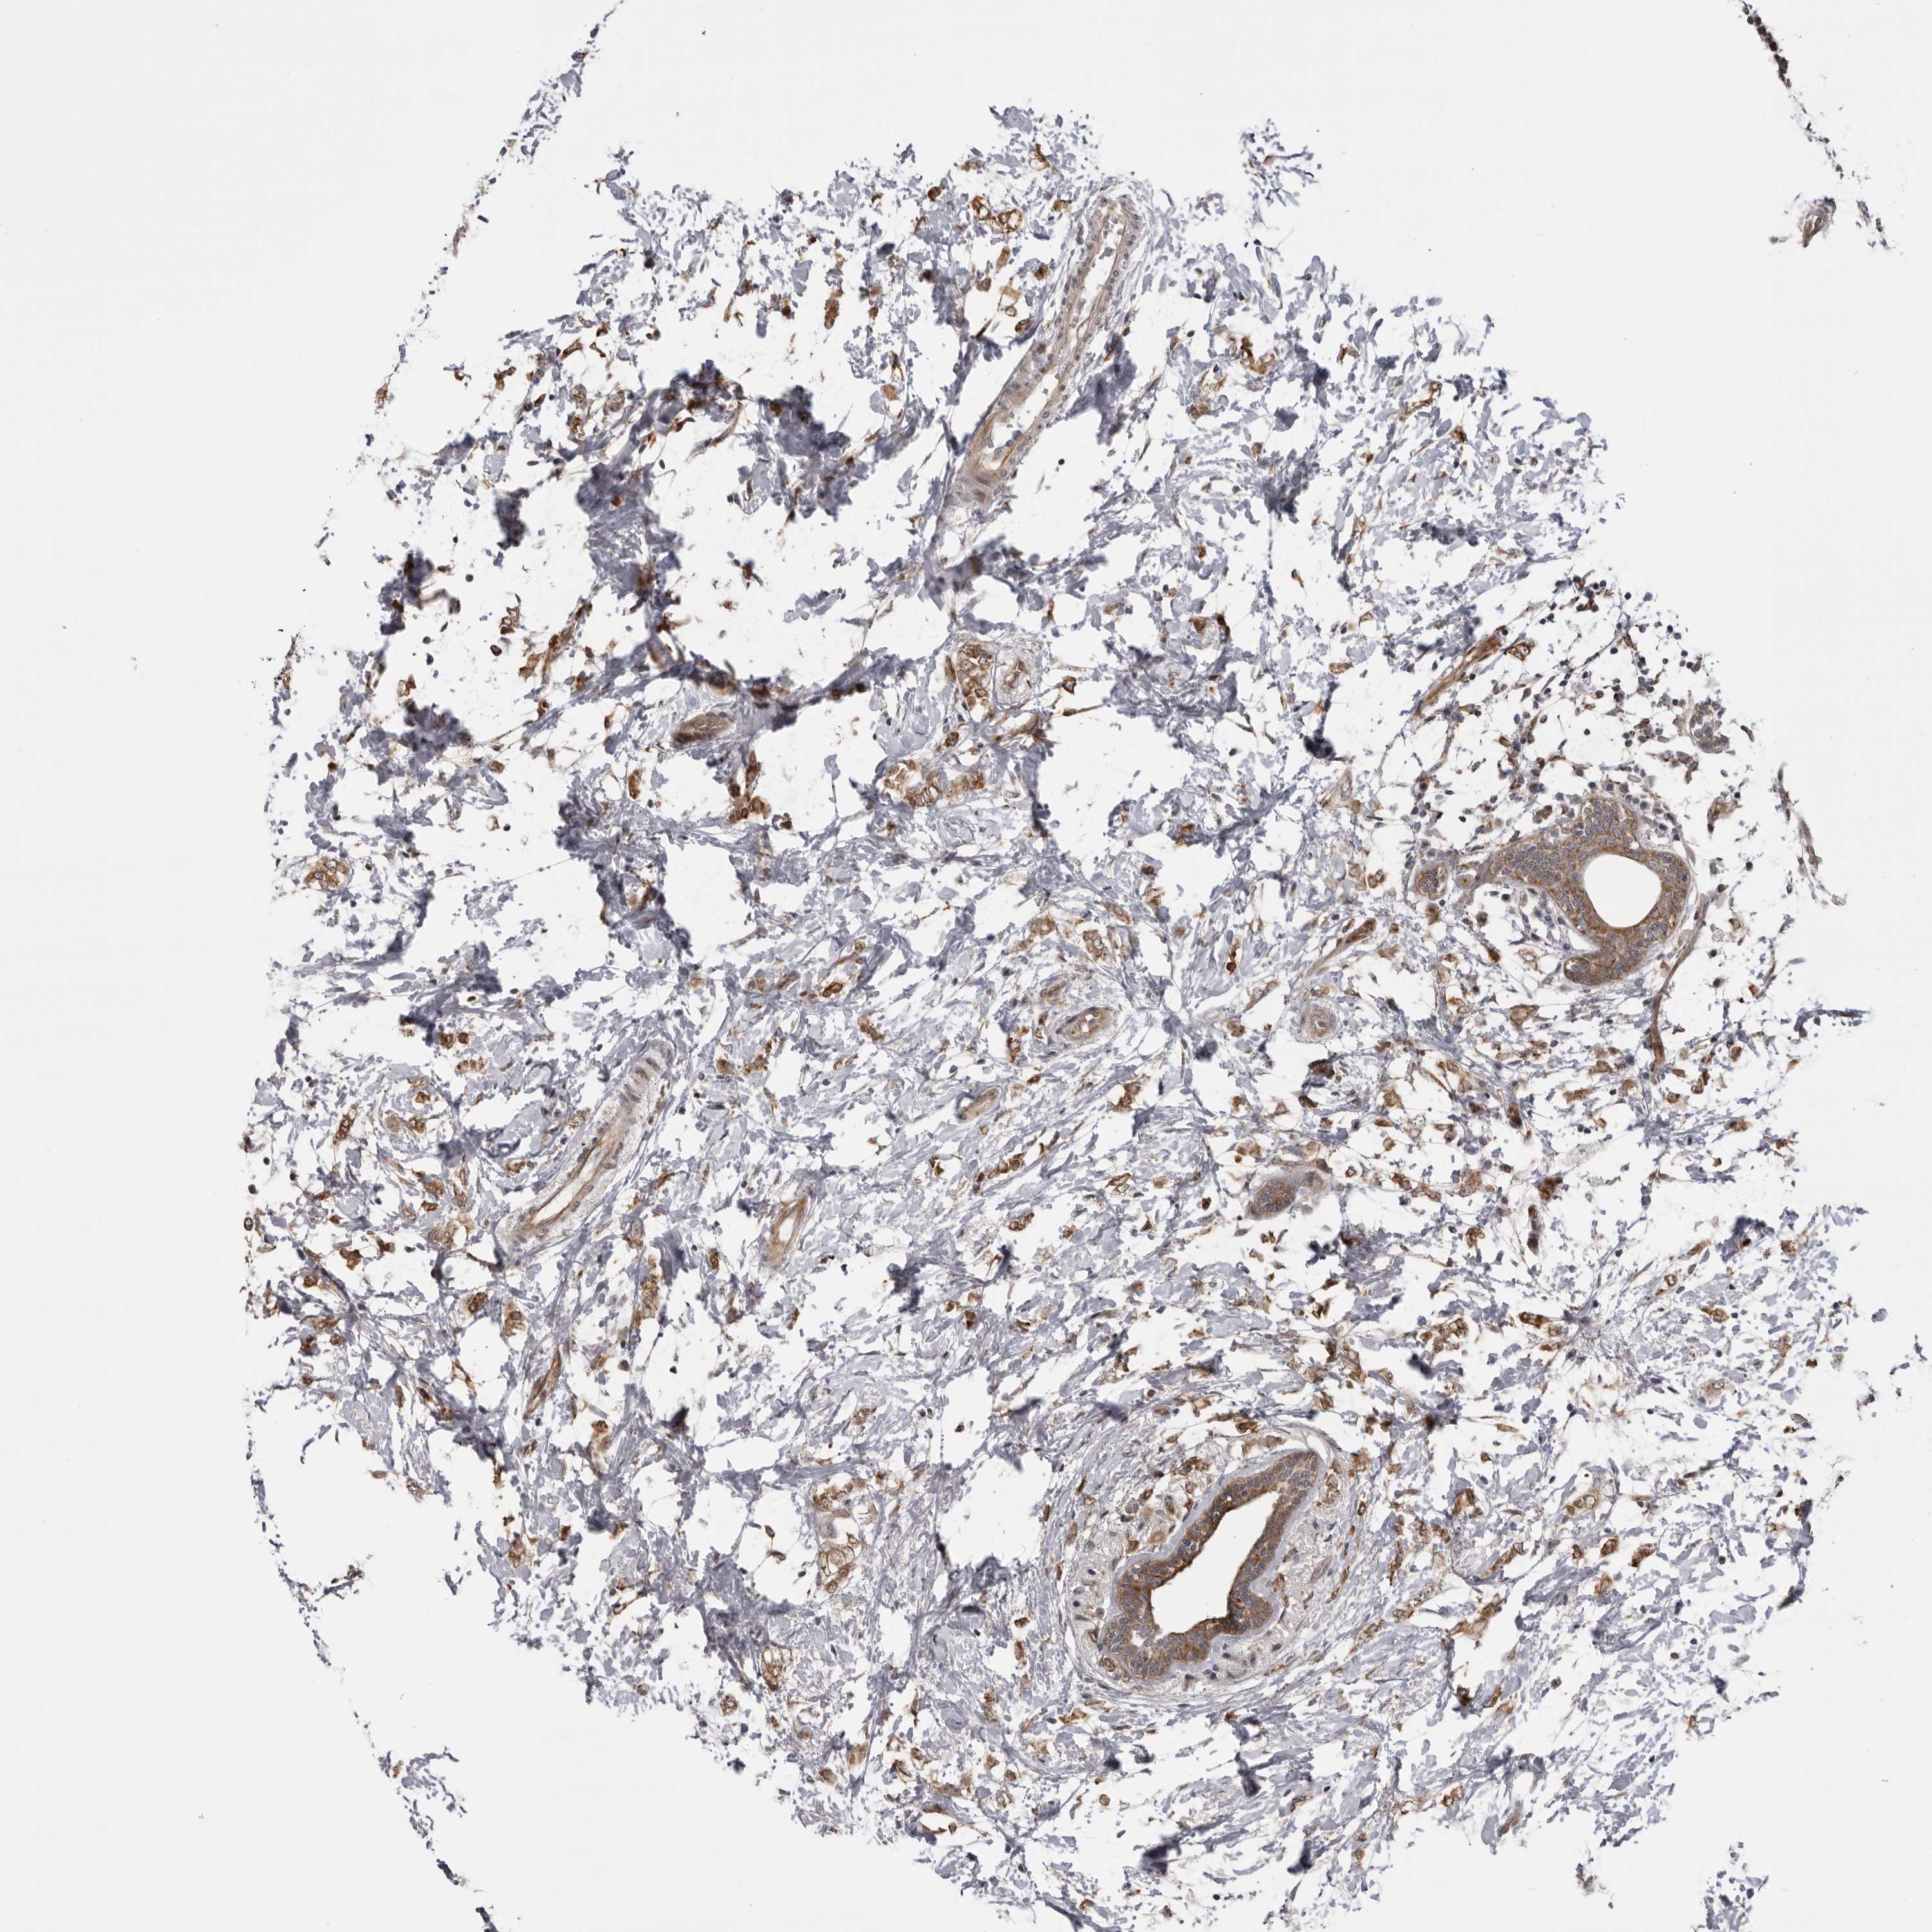

CANCER BREAST CANCER Show tissue menu

BRCA TCGA BRCA VALIDATION PROTEIN EXPRESSION